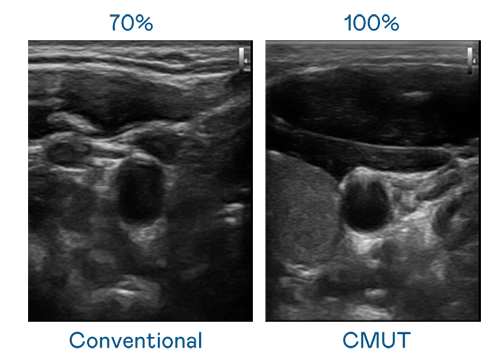

CMUT 技术是一种用电容式微机电元件来产生超音波讯号的技术。与传统 PZT 压电式技术相比,CMUT 频宽增加 30%,更宽频的超音波讯号让影像解析度大幅提升,是实现高影像品质医疗超音波扫描、促进精准医疗发展的关键技术。

超音波影像的解析度高低,首先取决于探头能发出的讯号频宽。美狮贵宾会 CMUT 可提供高清晰的超音波讯号,提供高频宽、高灵敏度、影像纹理细节更高的超音波影像,协助医护人员缩短影像判读时间及利用精准的医疗影像进行诊断。